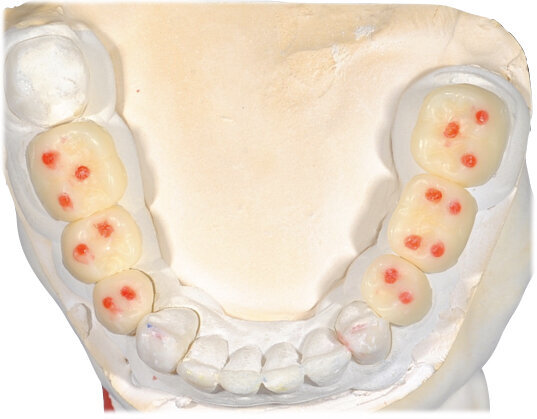

Ciò consente un miglioramento dei rapporti interarcata, un guadagno di spazio protesico in regioni premolari e molari, ed il mantenimento di uno spazio protesico conforme ad una corretta anatomia per i denti vitali da 1.3 a 2.3. Al paziente viene pertanto aggiornato il piano di trattamento e proposta la riabilitazione in TRP, con la previsione di overlays all’arcata inferiore per costruzione del nuovo piano occlusale. In posizione terapeutica sono modellati i coni delle centriche attive sui monconi sfilabili all’arcata inferiore, per la successiva individuazione al CAD con modulo articolatore del piano occlusale studiato. Questo rapporto articolare in TRP è ora scansito con scanner da laboratorio Xanos Evo Scan Compact (Fig. 24).

I modelli sono così importati in corretta posizione spaziale tramite il modulo exocad Virtual Articulator (Fig. 25). Non avendo a disposizione nel CAD l’analogo virtuale dell’articolatore Reference SL, viene impostato il sistema virtuale SAM, che usa lo stesso piano di riferimento axio-orbitale e geometria sovrapponibile al Reference SL. Per la programmazione virtuale dei parametri funzionali dell’articolatore si riesegue l’output dall’axiografia elettronica con Gamma Dental per SAM (Fig. 26). Si procede perciò ora con la modellazione CAD della ceratura mantenendo il riferimento dato dal piano occlusale individuato dai coni di centrica scansiti con l’articolatore (Fig. 27). L’articolatore virtuale consente una prima verifica dei rapporti occlusali tra gli elementi e un abbozzo di funzionalizzazione delle cuspidi con strumenti virtuali dinamici, che permette di arrivare ad un CAD design vicino alla morfologia ricercata (Figg. 28-33). Il modellato è ora fresato in cera Yeti Dental al CAM con fresatore VHF Cam5-S1 ed i denti in cera, tutti singolarmente sfilabili, sono posizionati sui modelli eseguiti con stampa 3D.

Il fresato ottenuto è poi riportato su articolatore Reference SL – già opportunamente programmato – e viene dall’Odontotecnico competente più precisamente funzionalizzato secondo i criteri della programmazione funzionale sequenziale, evidenziando con cere colorate i rapporti di centrica, le funzioni di mediotrusiva e protrusiva e le protezioni retrusive. I monconi sfilabili consentono la modellazione della sequenzialità mediotrusiva con la guida incisale indicata dalla registrazione axiografica (blu) (Figg. 34-37). La ceratura sequenziale è ora scansita con Sirona InEos X5 su Exocad, ed il modellato viene ricontrollato al CAD per spessori, connessioni e morfologia, e nella regolazione degli offsets per la ripreparazione dei monconi, ed è inviato al CAM per la fresatura dei II provvisori in Bredent breCAM.multicom, un PMMA con microriempitivo ceramico ad alta stabilità, su Dental Plus 5 Axis Milling Machine. La rifinitura dei monconi è seguita da ribasatura dei II provvisori in TRP - previo isolamento di tutte le superfici funzionali - e gli stessi sono poi rifiniti e lucidati. I soli elementi 3.3, 4.2 e 4.3 sono rimodellati in regione incisale con addictions in composito, secondo la morfologia studiata in ceratura. La consegna conferma la buona integrazione dei manufatti dal punto di vista estetico, occlusale, articolare e neuromuscolare, con controllo occlusale conforme al progetto (Figg. 38-42).